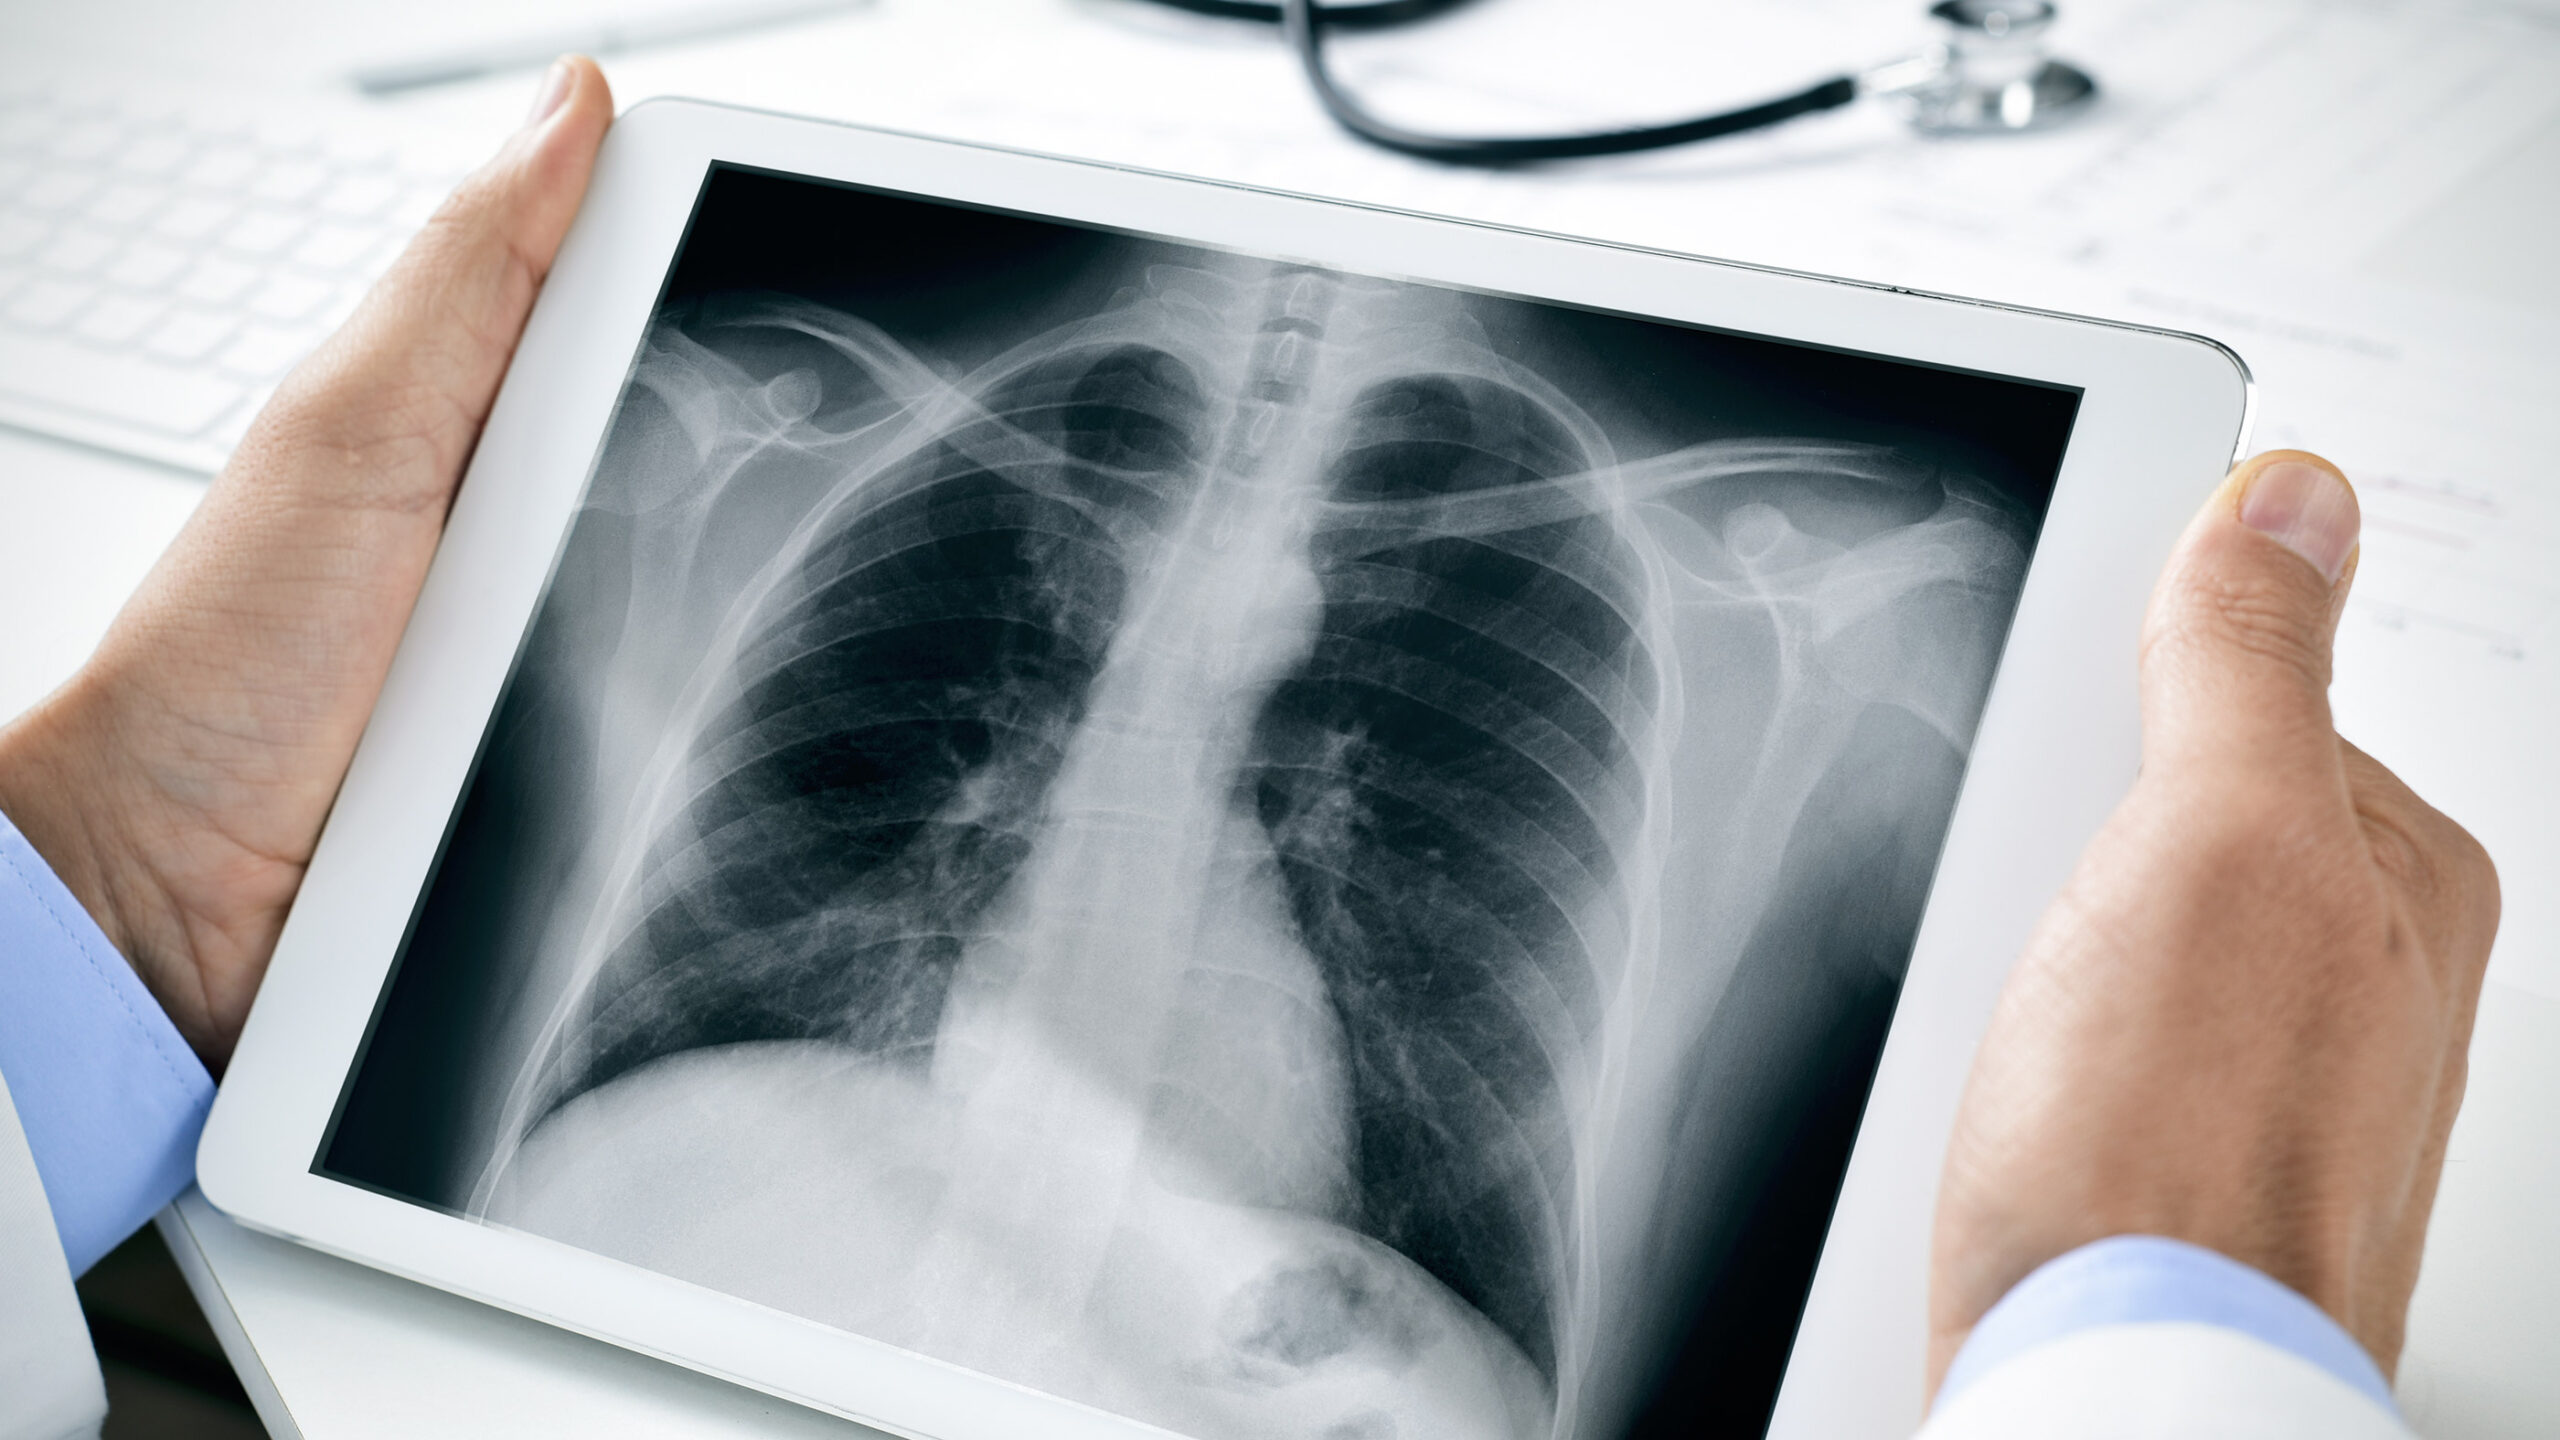

Healthcare organizations face mounting pressures to store vast amounts of medical imaging data generated from modalities like X-ray, MRI, CT, ultrasound, and endoscopy. These images are critical for diagnostics, treatment planning, and legal documentation, necessitating secure and reliable long-term storage solutions. The growth in high-resolution imaging has led to files that can reach several gigabytes per examination, significantly increasing storage demands. Consequently, hospitals must adopt advanced archiving systems capable of handling this data surge while maintaining quick access for medical staff across multiple locations.

A PACS, or “Picture Archiving and Communication System,” functions as a centralized digital platform for storing, managing, and retrieving medical images and associated data. It acts similarly to a comprehensive database, where every diagnostic image captured within a hospital is automatically stored on a dedicated server. This system integrates seamlessly with diagnostic devices such as X-ray machines, MRI scanners, CT units, and ultrasound devices, allowing for immediate storage and access of images.

To facilitate interoperability and consistent data handling, medical images are stored in a standardized format known as DICOM, or “Digital Imaging and Communication in Medicine.” This internationally adopted standard ensures that images can be securely exchanged and accurately interpreted across different systems and devices. Given the large size of high-quality DICOM files, PACS servers require ample storage capacity to accommodate the high data throughput, ensuring swift retrieval and management.